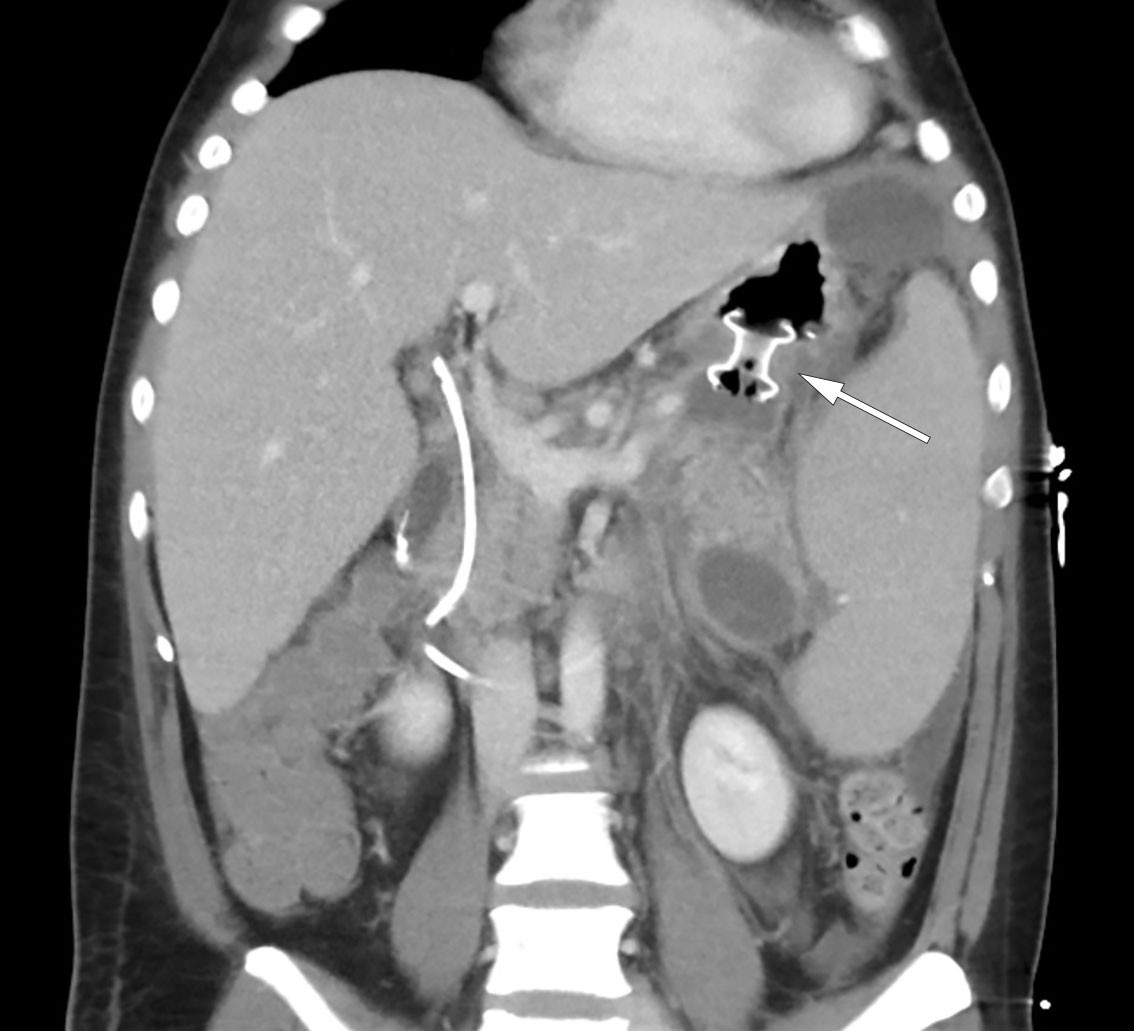

MRCP was performed the same day and revealed peripancreatic fluid collections and a 4 mm stone in the distal common bile duct (Figure 1). There were also pronounced signs of pancreatitis with surrounding oedema and fluid collections in the upper abdomen. By day 3 after admission, the patient's condition had worsened, and he was experiencing nausea and increased pain. Blood tests showed persistent leukocytosis at 45.6 × 109/L. His CRP level had increased to 261 mg/L, and his bilirubin level had increased further to 290 μmol/L. Broad-spectrum intravenous antibiotics were initiated in the form of piperacillin/tazobactam 4 g/0.5 g three times daily due to suspicion of concurrent infection in the biliary tract. The patient was also referred for endoscopic retrograde cholangiography (ERC), which was performed without complications, with papillotomy followed by removal of two black stones from the distal common bile duct. Cholangiography revealed the gallbladder to be full of stones. Later that day, the patient's bilirubin level was found to have decreased to 139 μmol/L.

Over the course of day 3, the patient's clinical condition deteriorated further and he developed severe abdominal pain. He was transferred to the intensive care unit due to incipient organ failure with a need for oxygen. He was somnolent and, although breathing independently, required 2–3 L of O2 via nasal catheter to maintain oxygen saturation above 92 %. His INR level had increased to 1.9 while his albumin level had fallen to 22 g/L (from 45.6 g/L), raising suspicion of a bleeding disorder. In addition, his bilirubin level had increased once again to 290 μmol/L, but in the absence of any other liver or bile enzyme increases, it was decided based on an interdisciplinary discussion not to proceed immediately with another ERC examination. Further diagnostic imaging with a CT scan of the abdomen and pelvis revealed necrotising pancreatitis with peripancreatic fluid collections and free fluid in the abdomen (Figure 2). There were no signs of intra- or extrahepatic cholestasis. However, bilateral pleural effusion and atelectasis were observed, which could explain the deterioration in respiratory function. Due to the patient's elevated INR level, a pleural tap was not performed. Enlargement of the spleen (21 cm in length) was also noted.